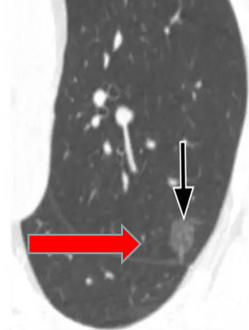

右下肺磨玻璃结节

2月后复查变淡消散